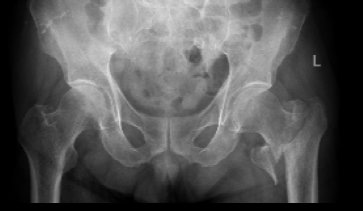

患者张爷爷已逾九旬,基础疾病错综复杂:前列腺癌病史3年、高血压20年、糖尿病30年,10天前因脑梗死导致左侧肢体活动不便。然而近日,厄运再次降临,他在家如厕时不慎跌倒,造成“左侧股骨转子间粉碎型骨折”,被紧急送至我院。

入院时,老人情况十分危急:除骨折外,还存在Ⅰ型呼吸衰竭、慢性支气管炎急性加重、低钠血症及贫血。入院后其呼吸功能进一步恶化,随即被转入ICU,进行气管插管、呼吸机辅助呼吸。经过ICU团队5天昼夜不停的全力救治,张爷爷的呼吸功能终于显著改善,成功拔管,脱离了生命危险。